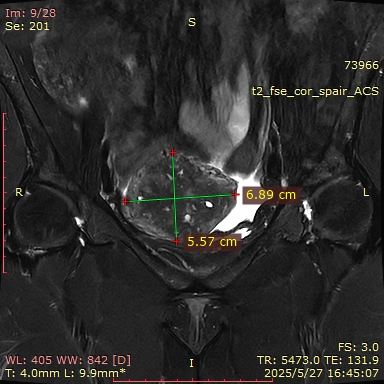

MRI(2025-05-27):子宫肌层增厚,其内信号欠均匀,肌层内见一等类圆形T2WI低信号,其内可见T1WI高信号,大小约为40mm*39mm。左侧附件区可见类圆形短T2异常信号影,大小约为8mm*5mm;右侧附件形态、大小、信号未见明显异常。盆腔少量积液。